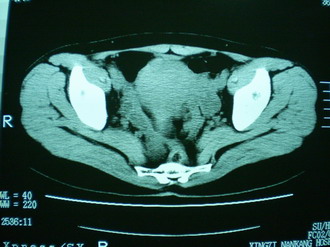

子宫增大,内可见类三角形低密度区,子宫后方可见类圆形团块状影,内部密度不均匀,可见靶样结构,结合病史考虑1子宫后方宫外孕(宫内假孕囊形成)2子宫肌瘤合并妊娠

子宫明显前倾,增大,宫颈增大呈分叶状。子宫直肠窝见不规则形水样低密度。(膀胱胀尿不理想)

考虑:1、宫颈部占位;

2、子宫直肠窝少量积液(盆腔炎所致)。

考虑:1、宫颈部占位(宫颈癌?);

2、子宫直肠窝少量积液。

1、前曲子宫,2、宫颈部占位?3、盆腔及右输卵管积液?宫内积血?4、左侧卵巢囊肿。